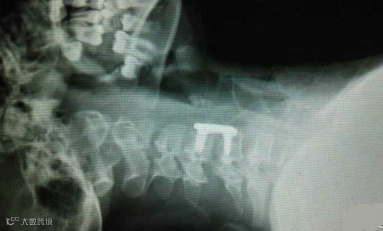

微信朋友圈,很多人都在为这位10岁的小姑娘祈祷。这就是她颈椎完全断裂的图片。

12月2日下午,她戴着长围巾乘坐电动车时,长围巾被车轮绞住。在惯性作用下,小青的脖子被紧紧勒住,电动车停下后,她感觉自己不能动了,而且呼吸也变得非常困难。经过手术,小青终于脱离危险,但由于脊柱断裂,小青已全身瘫痪。同时,意外还影响到了肌肉,小青已不能自主呼吸,目前只能通过呼吸机辅助呼吸。